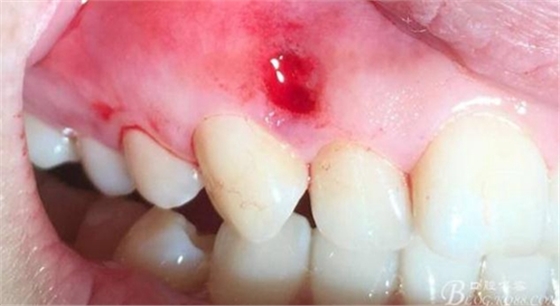

術(shù)后24小時(shí)

術(shù)后3日